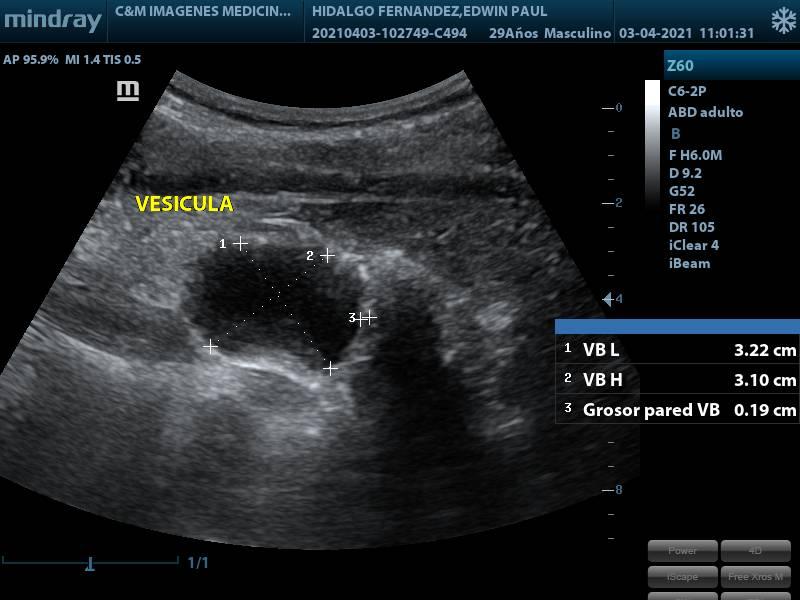

ECOGRAFIA ABDOMEN SUPERIOR

SERVICIOECOGRAFIA

CONDICIÓNEN AYUNA

ESPECIFICACIONESSE ESTUDIA: HIGADO PANCREAS VESICULA BILIAR RIÑONES BAZO VIAS BILIARES